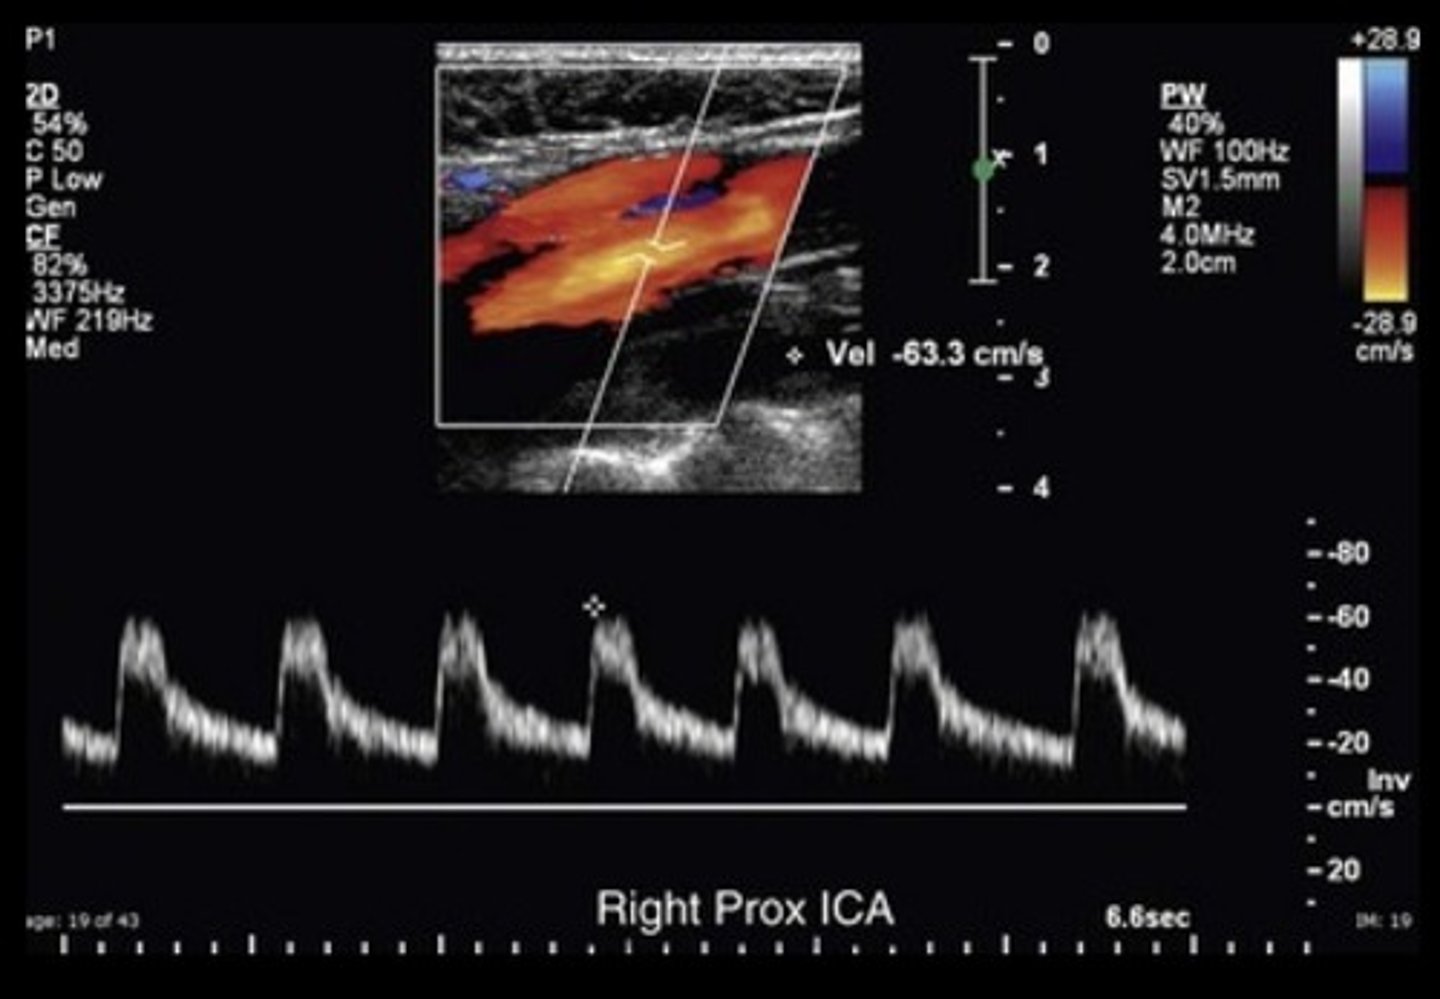

Prox ICA - just after bulb

Normal Prox CCA Waveform

Normal CCA Waveform

Normal ICA Waveform